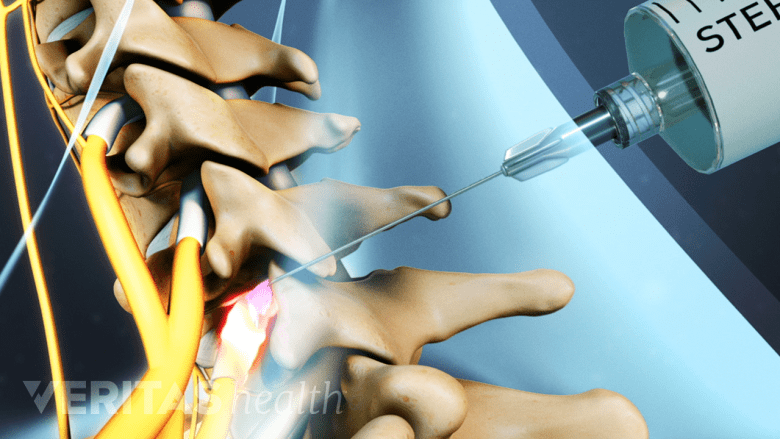

Nerve block injections are used to identify the origin of pain in the cervical spine.

Diagnostic nerve block injections are used to test the exact source of pain in the cervical spine. The technique involves injecting a pain-relieving anesthetic or anti-inflammatory solution around the nerve/joint. Medical imaging such as fluoroscopy (x-ray guidance) accompanied by contrast is used to guide the needle to the correct spot. Pain relief from these injections may be seen in all areas innervated by the nerve, including regions in the head.

See Selective Nerve Root Block Injections